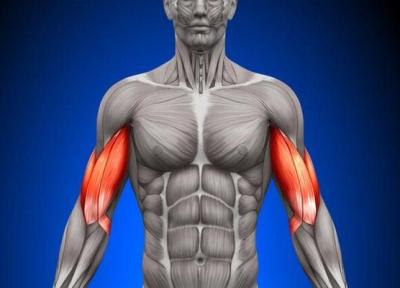

کشف پروتئینی که در ترمیم و رشد عضلات نقش دارد

میوکین ها (Myokines) پروتئین های کوچکی هستند که به وسیله سلول های ماهیچه اسکلتی ترشح می شوند. آن ها طیف گسترده ای از عملکرد ها را دارند و ممکن است روی سلول هایی که به محل ساخت آن ها نزدیک یا دور هستند، تاثیر بگذارند. تصویر جامع چگونگی تأثیر میوکین ها بر...